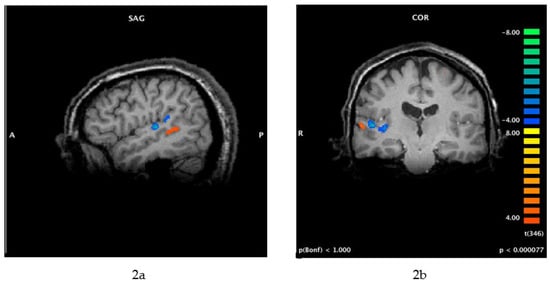

- Folmer, R.L. Lateralization of Neural Activity Associated with Tinnitus. Neuroradiology 2007, 49, 689–691. [Google Scholar] [CrossRef] [PubMed]